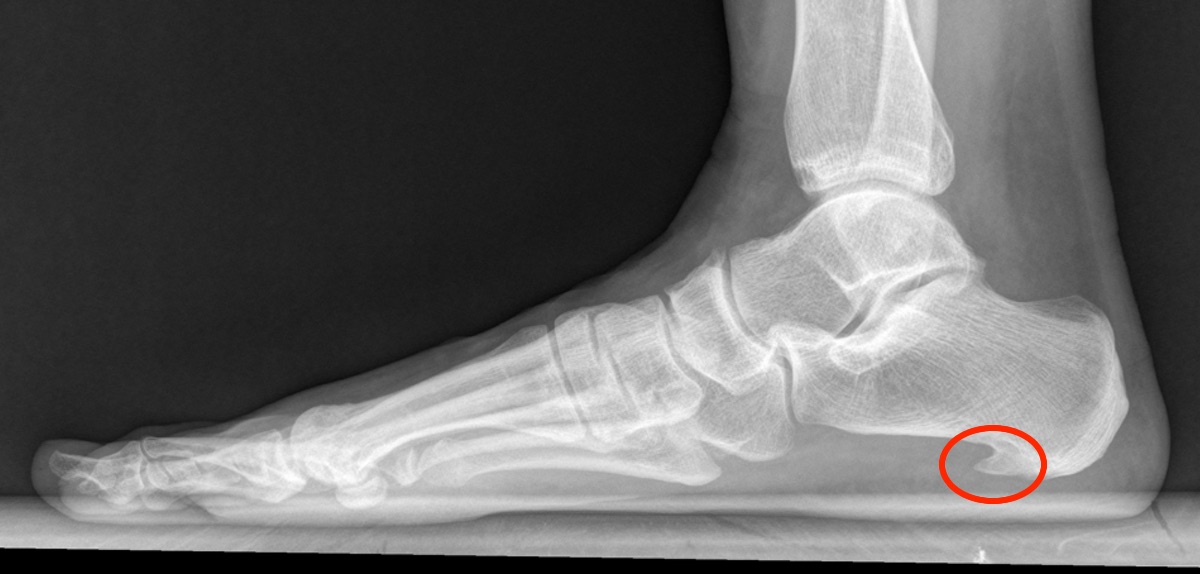

hielspoor-roentgen Gepubliceerd 21/04/2023 at 1200 × 574 in Wandelen en hielspoor: wat je er (niet) aan kunt doen ← Vorige Volgende → Hielspoor zichtbaar op Röntgen-foto